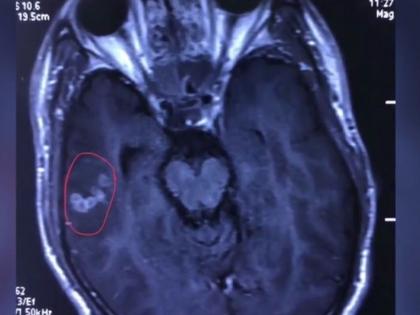

(Image Credit : asiaone.com) (झांग यांच्या मेंदूतून काढलेला किडा)

नंतर ते पुन्हा एकदा डॉक्टरकडे गेले. पण डॉक्टरांनी त्यांना पुन्हा तेच फिट येण्याचं कारण सांगितलं. मात्र, झांग हे दुसऱ्या डॉक्टरकडे गेले. त्यांनी झांग यांचा एमआरआय स्कॅन केला. तेव्हा त्यांचं डोकेदुखीचं खरं कारण समोर आलं. झांग यांच्या मेंदूत एक १० सेंटीमीटर लांब किडा होता. हा किडा सर्जरी करून काढण्यात आला. यात सर्वात आश्चर्यकारक बाब म्हणजे हा किडा गेल्या ३० वर्षापासून जिवंत होता. हे पाहून डॉक्टरही चक्रावून गेले होते.